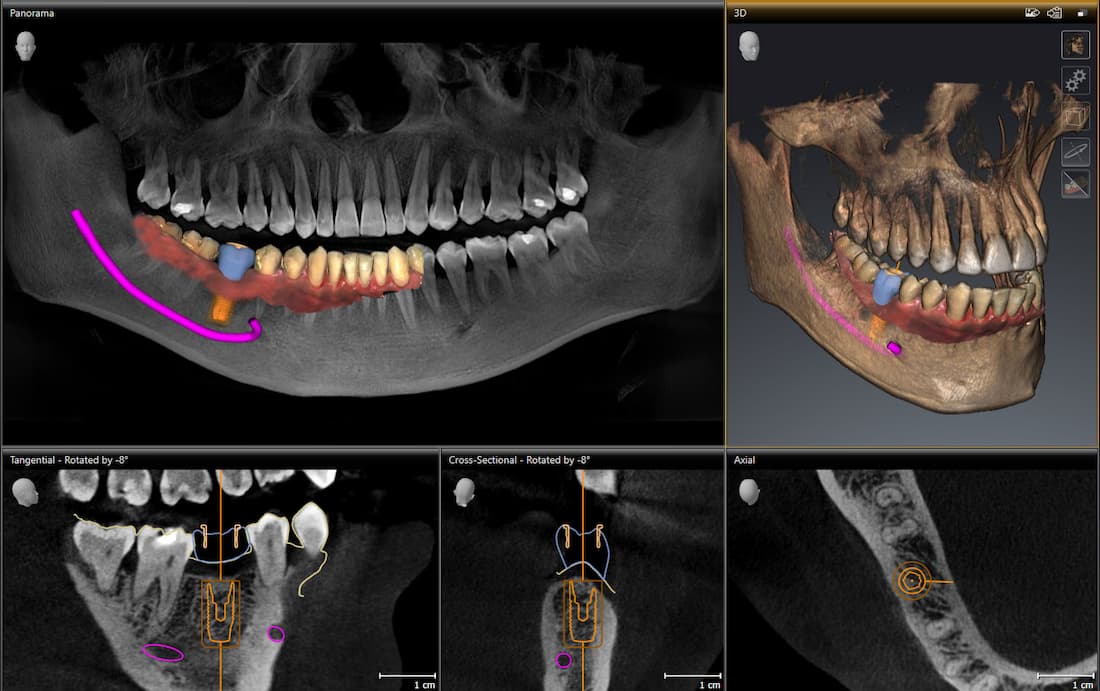

Haben wir das digitale Abbild Ihres Kiefers erstellt, können wir in realistischem 3D die Implantate am PC computergestützt planen. Bei der sog. computergestützten 3D-Implantatplanung ermöglicht uns die Software, die perfekte Position, den idealen Winkel und auch die optimale Tiefe für Ihre Zahnimplantate zu finden, immer unter Berücksichtigung des Knochenangebots, das bei jedem Menschen anders ist. Außerdem haben wir bei der Planung von Zahnimplantaten so auch die Nachbarzähne im Blick und können kritische Strukturen wie Nerven, Kieferhöhle und Nasenhöhle sicher umgehen. Erst wenn wir die Implantation erfolgreich am Bildschirm simuliert haben und mit dem Ergebnis der digitalen 3D-Implantatplanung zufrieden sind, folgt der nächste Schritt.

Quelle: Dentsply Sirona